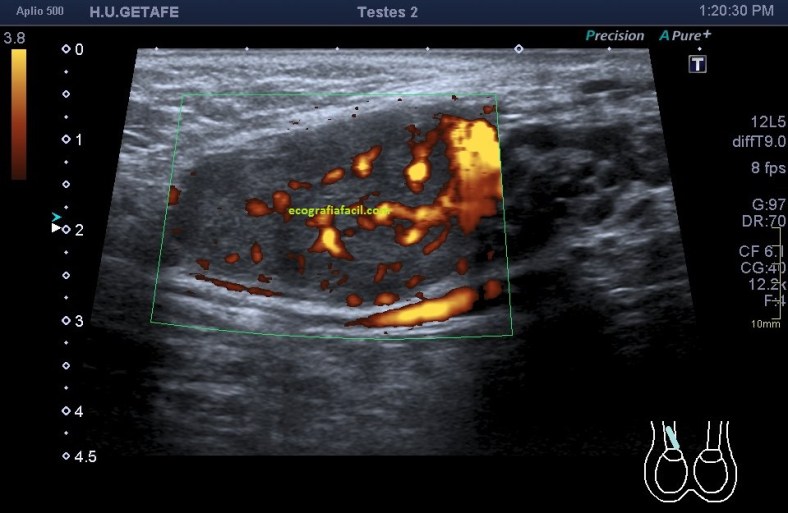

311. Doppler color y Modo Angio, dos secretos que igual no sabías.

Cuando realizamos una exploración ecográfica, el protocolo que sea, no es raro que uno de los comandos que más usemos sea el Doppler, sabemos cómo funciona el Doppler, Alejandro lo ha explicado en este blog y el libro Eco Fácil de Marbán, pero yo quiero contarte dos secretos, que seguro que sabes, pero que quiero contarlo por si hay alguien un poquito más rezagado que aún no se ha enterado.

Quiero que te preguntes si sabrías diferenciar entre una imagen Doppler Color y una imagen en Modo Angio o Doppler Power. Vas a decir que sí, que lo sabes. Y es cierto, en la mayoría de las ocasiones distinguimos estas dos técnicas por el color, una rojo y azul, otra azul o morado, u otras coloraciones según la casa comercial.

Modo Doppler Color

Modo Angio o Doppler Power

Ahora quiero que te preguntes si sabrías decirte que magnitud de la onda ultrasonográfica toma de referencia cada una de los dos comando cuando los activamos para darnos la imagen que estamos buscando…igual aquí tienes alguna dificultad, igual aquí, te he pillado¿Te sonríes?…me encanta…ah que ya lo sabes…bueno, pues lo voy a explicar para quien no lo sepa.

En la onda ultrosonográfica hay dos magnitudes claves, la longitud de onda, que es la distancia entre dos puntos de una misma onda, por ejemplo, entre sus valles o entre sus crestas, que será menor cuanto más alta sea la frecuencia, y la amplitud de la onda que es la máxima distancia que alcanza la onda, o de otro modo, lo enérgica que es esa onda.

Muy bien, en el Doppler Color (CDI) la magnitud de referencia que tomará nuestro equipo para hacer la medición de aquello que estemos interesados en estudiar será la longitud de onda. Sin embargo, en el Doppler Power o Modo Angio (Power) el equipo lee la Amplitud de la onda ultrasonográfica, la imagen de abajo.

Otra de las diferencias entre estos modos de trabajo si lo quieres llamar así es la medición de los hematíes. Me explico, cuando estamos haciendo Doppler lo que medimos es el movimiento hístico. No estamos midiendo las características ecográficas del tejido, es decir, no queremos saber si es anecoico, hipo o hiperecogénico, estamos midiendo su movimiento, el de los vasos, o el de las estructuras que puedan estar vascularizadas.

Por tanto este modo de trabajo valoriza el movimientos de los hematíes, su velocidad, y la densidad de estas células sanguíneas las mide el modo angio, por eso el Doppler color se usa para flujos rápidos (medidad cuantitativa) y el modo angio para flujos lentos (medida cualitativa), por eso el modo angio es mas sensible, así que si eres muy sensible, eres modo angio… ¿lo entiendes?